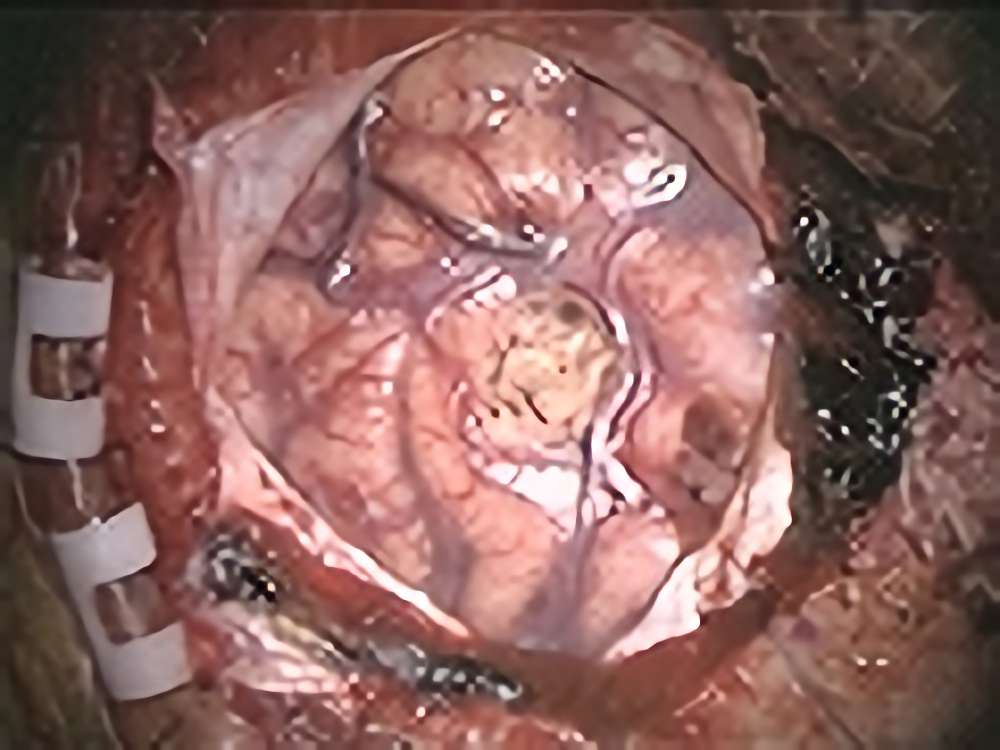

頭頂葉海綿状血管腫

No.’13_169 手術前1

No.’13_169 摘出 前

No.’13_169 摘出 後